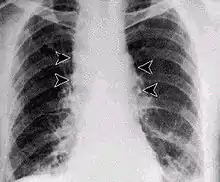

Inhalation anthrax usually develops within a week after exposure, but may take up to 2 months.[27] During the first few days of illness, most people have fever, chills, and fatigue.[27] These symptoms may be accompanied by cough, shortness of breath, chest pain, and nausea or vomiting, making inhalation anthrax difficult to distinguish from influenza and community-acquired pneumonia.[27] This is often described as the prodromal period.[27]

Over the next day or so, shortness of breath, cough, and chest pain become more common, and complaints not involving the chest such as nausea, vomiting, altered mental status, sweats, and headache develop in one-third or more of people.[27] Upper respiratory tract symptoms occur in only a quarter of people, and muscle pains are rare.[27] Altered mental status or shortness of breath generally brings people to healthcare and marks the fulminant phase of illness.[27]

It infects the lymph nodes in the chest first, rather than the lungs themselves, a condition called hemorrhagic mediastinitis, causing bloody fluid to accumulate in the chest cavity, thereby causing shortness of breath. The second (pneumonia) stage occurs when the infection spreads from the lymph nodes to the lungs. Symptoms of the second stage develop suddenly within hours or days after the first stage. Symptoms include high fever, extreme shortness of breath, shock, and rapid death within 48 hours in fatal cases.[28]